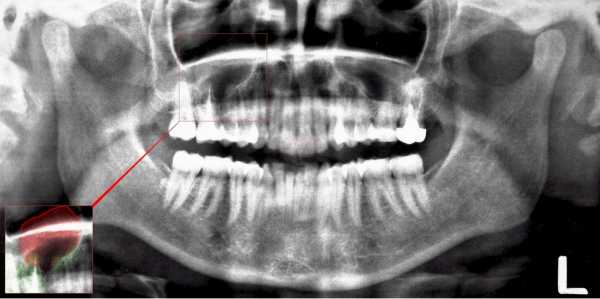

| Ортопантомограмма | С помощью снимка высокого качества, выполненного на цифровом оборудовании, можно достоверно определить размер и место образования кистозного мешочка (справа или слева, снизу или сверху). |

Киста правой верхнечелюстной пазухи носа на снимке

Рентген пазух носа. На снимке киста представляет собой образование округлой формы, которое выпирает на одной из стенок исследуемой гайморовой пазухи. Оно обладает четким гладким контуром. Однако подобная диагностика является результативной только в том случае, если размеры кисты большие. Еще один вариант установления диагноза – рентгенограмма с использованием контраста. С его помощью можно обнаружить образования любых габаритов.

Рентгенография помогает выявить достаточно крупные опухоли. На снимке они выглядят как круглые выпячивания на одной из стенок пазух носа с гладкими контурами. В медицине используют рентген с контрастом, который позволяет определить новообразование разного размера с обеих сторон. При одонтогенной кисте верхней челюсти в альвеолярной бухте врач выбирает другую проекцию для создания снимка.